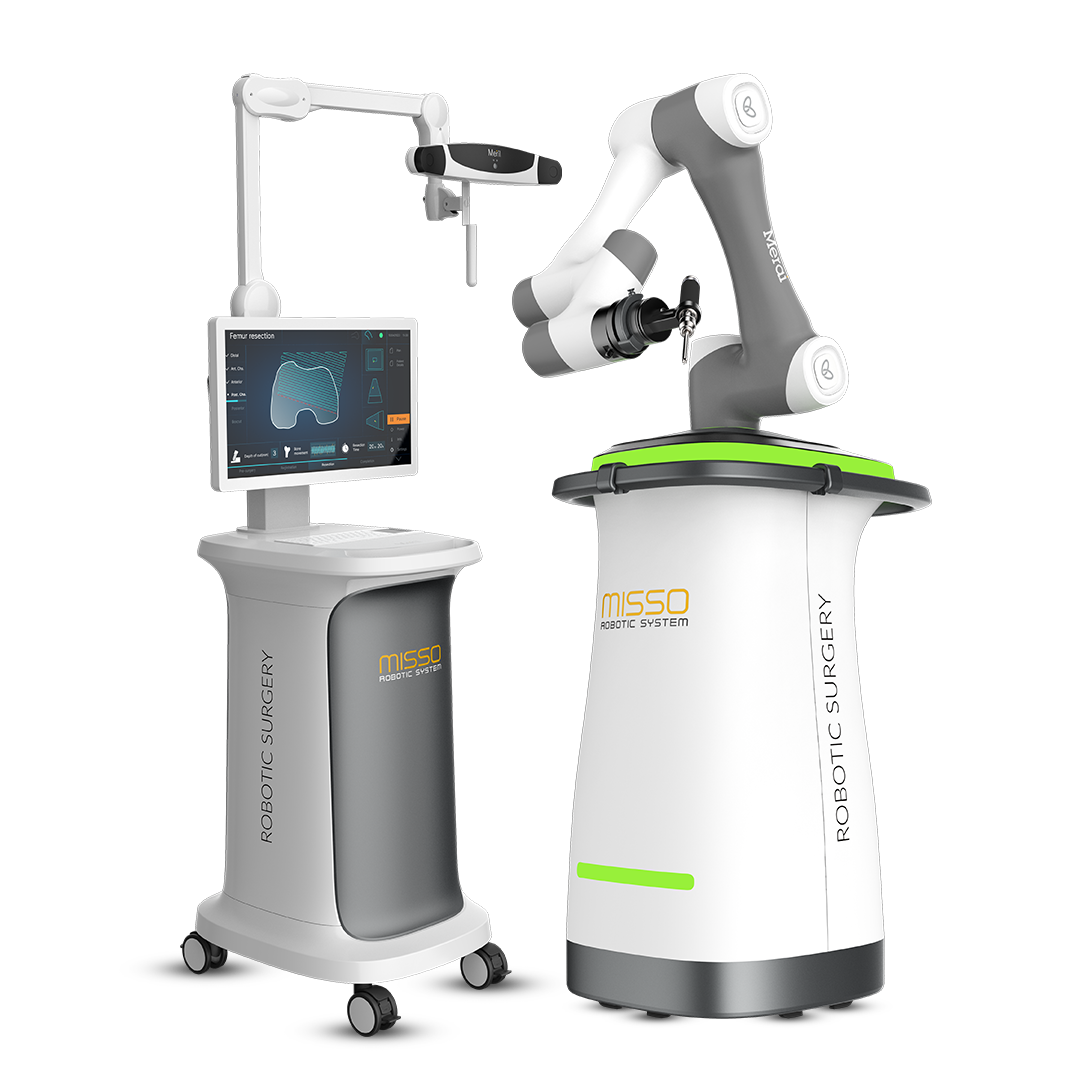

Introduction to MISSO Robotic System

At MM Multi-Speciality Hospital, we are proud to introduce the MISSO Robotic System, the latest innovation in total knee replacement surgery in Namakkal, Tamil Nadu. This state-of-the-art technology redefines precision and personalization in medical procedures, offering patients a safer, more accurate, and efficient surgical experience.

The MISSO Robotic System is equipped with a 6-axis articulated robotic arm, an optical tracking sensor (NDI Polaris), and superior safety sensors to ensure maximum precision during surgery.

The system includes real-time bone movement monitoring and an emergency stop feature. If any bone movement is detected during surgery, the robotic system immediately halts the resection process, enhancing patient safety.

MISSO Robotic System performs fully automatic bone resection without requiring cutting guides, reducing the potential for human error. This automated process enhances surgical accuracy and safety.

The MISSO Robotic System provides surgeons with real-time assistance during surgery, allowing precise adjustments to implant placement and ensuring optimal fit.

The system offers faster segmentation, quick setup, and an optimized surgical procedure cycle, significantly reducing surgery time and improving operating room efficiency.

Due to the robotic system’s precision, the surgery results in minimal tissue damage, reducing post-operative pain and accelerating recovery.

Patients undergoing MISSO Robotic knee surgery experience shorter hospital stays, quicker recovery, and a faster return to daily activities due to the system’s precision and efficiency.

The system creates patient-specific 3D models from CT scans, allowing surgeons to plan and execute surgeries tailored to each individual’s unique anatomy.

The MISSO Robotic System is equipped with a 6-axis articulated robotic arm, an optical tracking sensor (NDI Polaris), and superior safety sensors to ensure maximum precision during surgery.

The system includes real-time bone movement monitoring and an emergency stop feature. If any bone movement is detected during surgery, the robotic system immediately halts the resection process, enhancing patient safety.

MISSO Robotic System performs fully automatic bone resection without requiring cutting guides, reducing the potential for human error. This automated process enhances surgical accuracy and safety.

The system offers faster segmentation, quick setup, and an optimized surgical procedure cycle, significantly reducing surgery time and improving operating room efficiency.

Due to the robotic system’s precision, the surgery results in minimal tissue damage, reducing post-operative pain and accelerating recovery.

Patients undergoing MISSO Robotic knee surgery experience shorter hospital stays, quicker recovery, and a faster return to daily activities due to the system’s precision and efficiency.

At MM Multi-Speciality Hospital, we are committed to providing the best care using the latest medical technologies. The introduction of the MISSO Robotic System ensures that our patients receive knee replacement surgeries that are safer, more accurate, and less invasive than traditional methods. Our team of expert orthopedic surgeons is trained to leverage the capabilities of the MISSO system to deliver exceptional outcomes.

If you or a loved one is considering knee replacement surgery, MM Multi-Speciality Hospital in Namakkal, Tamil Nadu invites you to explore the benefits of the MISSO Robotic System. Our personalized and precise approach ensures a faster recovery and better post-operative outcomes.

Experience the future of knee replacement surgery with the MISSO Robotic System—Precision, Personalization, and Care, all in one.